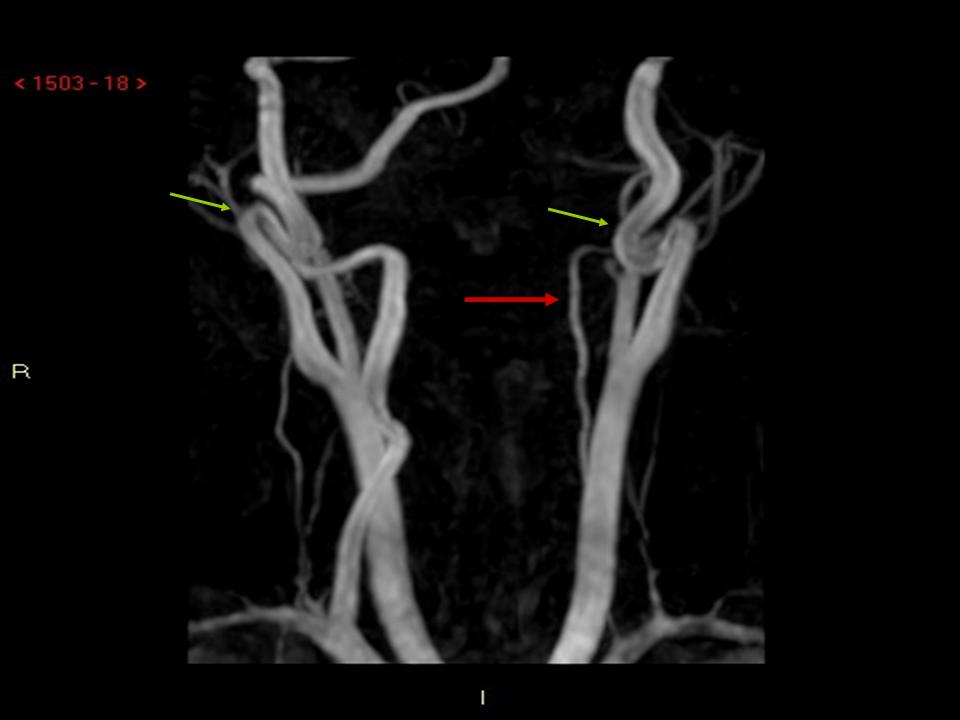

Figura

2. RMN. Coronale TSE T2: piccola lesione iperintensa a carico della porzione posteriore del bulbo compatibile con piccola lesione ischemica recente.

3. Angio-RMN. PC vasi epiaortici: marcata asimmetria di calibro delle arterie vertebrali per ipoplasia dell�arteria vertebrale sinistra (freccia rossa). Tortuosit� di decorso con kinking del tratto extracranico delle arterie carotidi interne (freccia verde).

La RMN encefalo con studio angiografico ha documentato una piccola area

iperintensa a livello della porzione posteriore laterale sinistra del

bulbo compatibile con lesione ischemica recente e marcata asimmetria

delle arterie vertebrali (dx > sin). Il corteo sintomatologico

presentato da E. � conseguente all�ischemia bulbare da

riduzione del flusso ematico in arteria vertebrale ed �

definito sindrome di Wallenberg(Box 1).